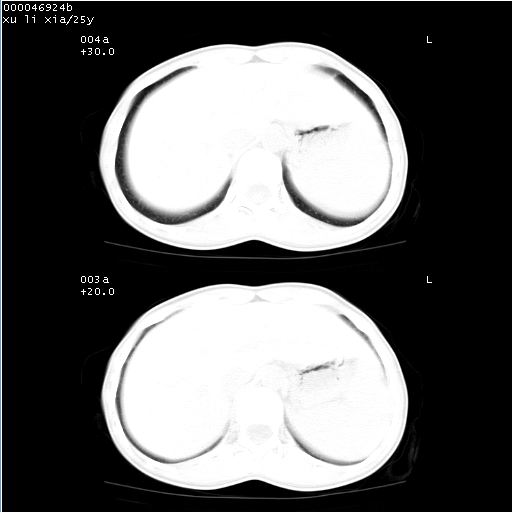

患者 女,25岁。因“左侧卵巢肿瘤”术前胸片偶然发现两肺病变。平素无明显不适,无呼吸系统症状及体征,无传染病史。

cr x线胸片提示:两肺感染性病变(结核可能性大)。

胸部ct轴位平扫(层厚10mm,螺距1.5,重建间隔10mm),图像如下:

(注:上级医院会诊胸部ct片——考虑为肺部真菌感染。)

病灶呈地图样分布于肺外围,与正常组织分界清晰+弥漫性磨玻璃影中见小叶间隔增厚呈碎石路样表现+年轻女性,无明显临床症状=肺泡蛋白沉积症?